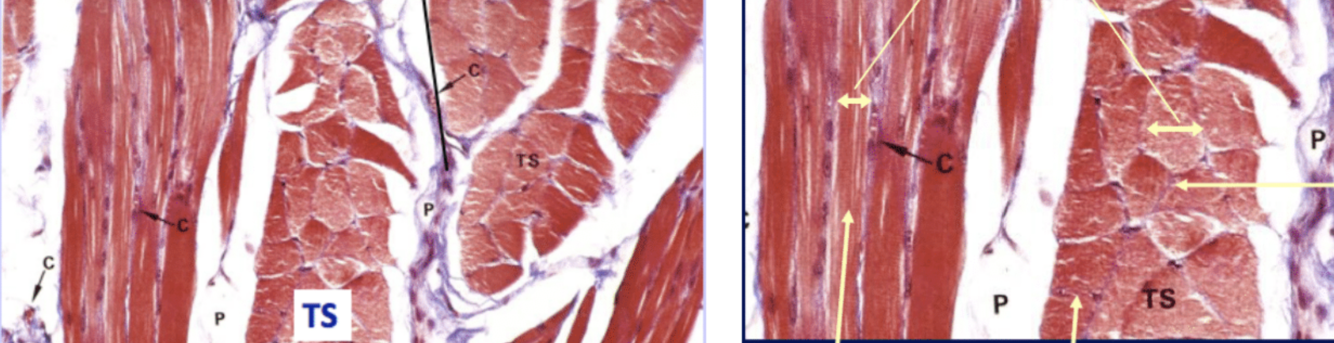

Below shows fascicles under a trichrome strain, showing that hay mas clear subdivisions.

LS=longitudinal section and TS= transverse section

Each fascicle has many muscle fibers (these are muscle cells)

Fine connective tissue around each fiber is called endomysium

Each cell is further split into myofibrils, these are contractile threads found in muscle cells